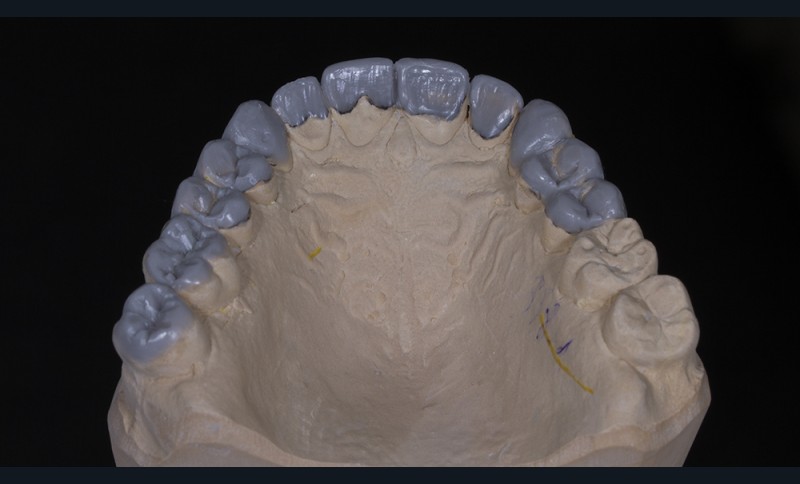

Le wax-up est préférentiellement élaboré en deux temps [17] : un wax-up dit esthétique, concernant uniquement les faces vestibulaires des dents de 15 à 25 puis un wax-up complet.

Dans un deuxième temps, un wax-up global permet de restaurer les courbes d’occlusion. Il est à noter que la présence d’égressions dentaires, faute d’antagoniste ou d’anciennes restaurations prothétiques inadaptées, crée des usures inégales au sein de la cavité buccale. Aussi, la présence de zones non recouvertes par le wax-up dans les secteurs postérieurs est courante, permettant ainsi la préservation de zones amélaires majeures pour le collage (fig. 2).

Le wax-up est le point de départ pour la réalisation de temporisations en technique d’isomoulage. Pour cela, le repositionnement de la clé en silicone s’effectue grâce à la réalisation de butées d’enfoncement sur des zones non waxées ou volontairement déwaxées (fig. 3).